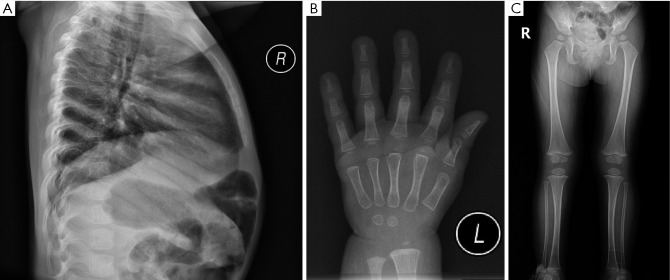

Case description: In this report, a female child is described who exhibited slow weight and height gain since birth. At 18 months, physical examination revealed that her height was below the 3rd percentile, with bone age delayed by 3 months. No typical NS facial features or congenital heart defects were observed. GH stimulation testing indicated partial GH deficiency, and the insulin-like growth factor 1 (IGF-1) level was below normal; thus, a preliminary diagnosis of short stature due to GH insufficiency was made, and nutritional intervention was recommended. However, follow-up revealed a persistent slow growth velocity and progressive bone age delay. At 6 years and 1 month of age, whole-exome sequencing identified a heterozygous c.923A>G (p.Asn308Ser) variant in the PTPN11 gene, confirming the diagnosis of NS. Recombinant human growth hormone (rhGH) therapy was subsequently initiated. After rhGH intervention, the patient's annual height velocity increased by 2.4 to 3.2 times compared to pretreatment, which was accompanied by synchronous progression of bone age.